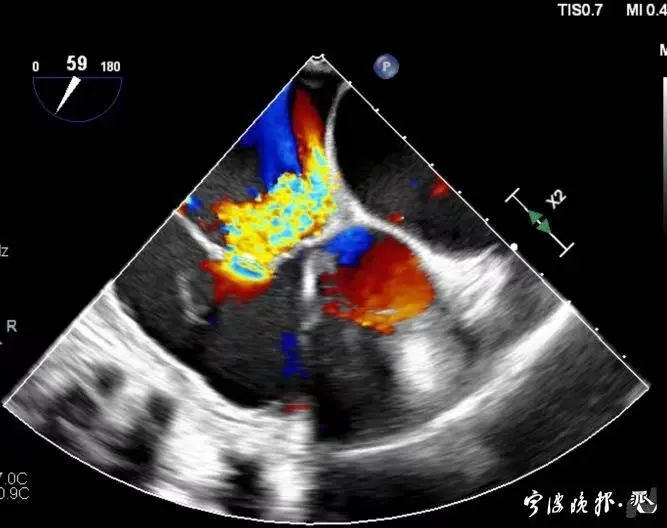

術(shù)前食道心超示三尖瓣重度反流

得知可以微創(chuàng)手術(shù),陳大爺一家決定放手一搏。寧波市醫(yī)療中心李惠利醫(yī)院心臟瓣膜中心團(tuán)隊(duì)反復(fù)就術(shù)前準(zhǔn)備、手術(shù)步驟及術(shù)后可能出現(xiàn)的各種情況做了預(yù)案。3月4日,陳大爺?shù)氖中g(shù)成功進(jìn)行,術(shù)中得到LuX-Valve經(jīng)導(dǎo)管三尖瓣置換術(shù)原創(chuàng)團(tuán)隊(duì),上海長海醫(yī)院陸方林主任團(tuán)隊(duì)的鼎力支持,術(shù)后陳大爺?shù)男呐K三尖瓣反流立即消失。術(shù)后瓣膜中心CCU(心臟監(jiān)護(hù))團(tuán)隊(duì)和心內(nèi)科團(tuán)隊(duì)迎接一個又一個右心瓣膜置換后的血流動力學(xué)改變等帶來的挑戰(zhàn),克服種種難關(guān),二周后患者進(jìn)入早期心臟康復(fù)。目前陳大爺已經(jīng)順利出院,沒有胸悶氣急,生活自理,精神狀態(tài)也很好,瓣膜中心團(tuán)隊(duì)也在對他持續(xù)隨訪中。